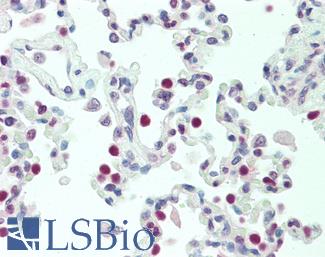

TP53

IHC of paraffin-embedded Carcinoma of Human lung tissue using anti-TP53 mouse monoclonal antibody.